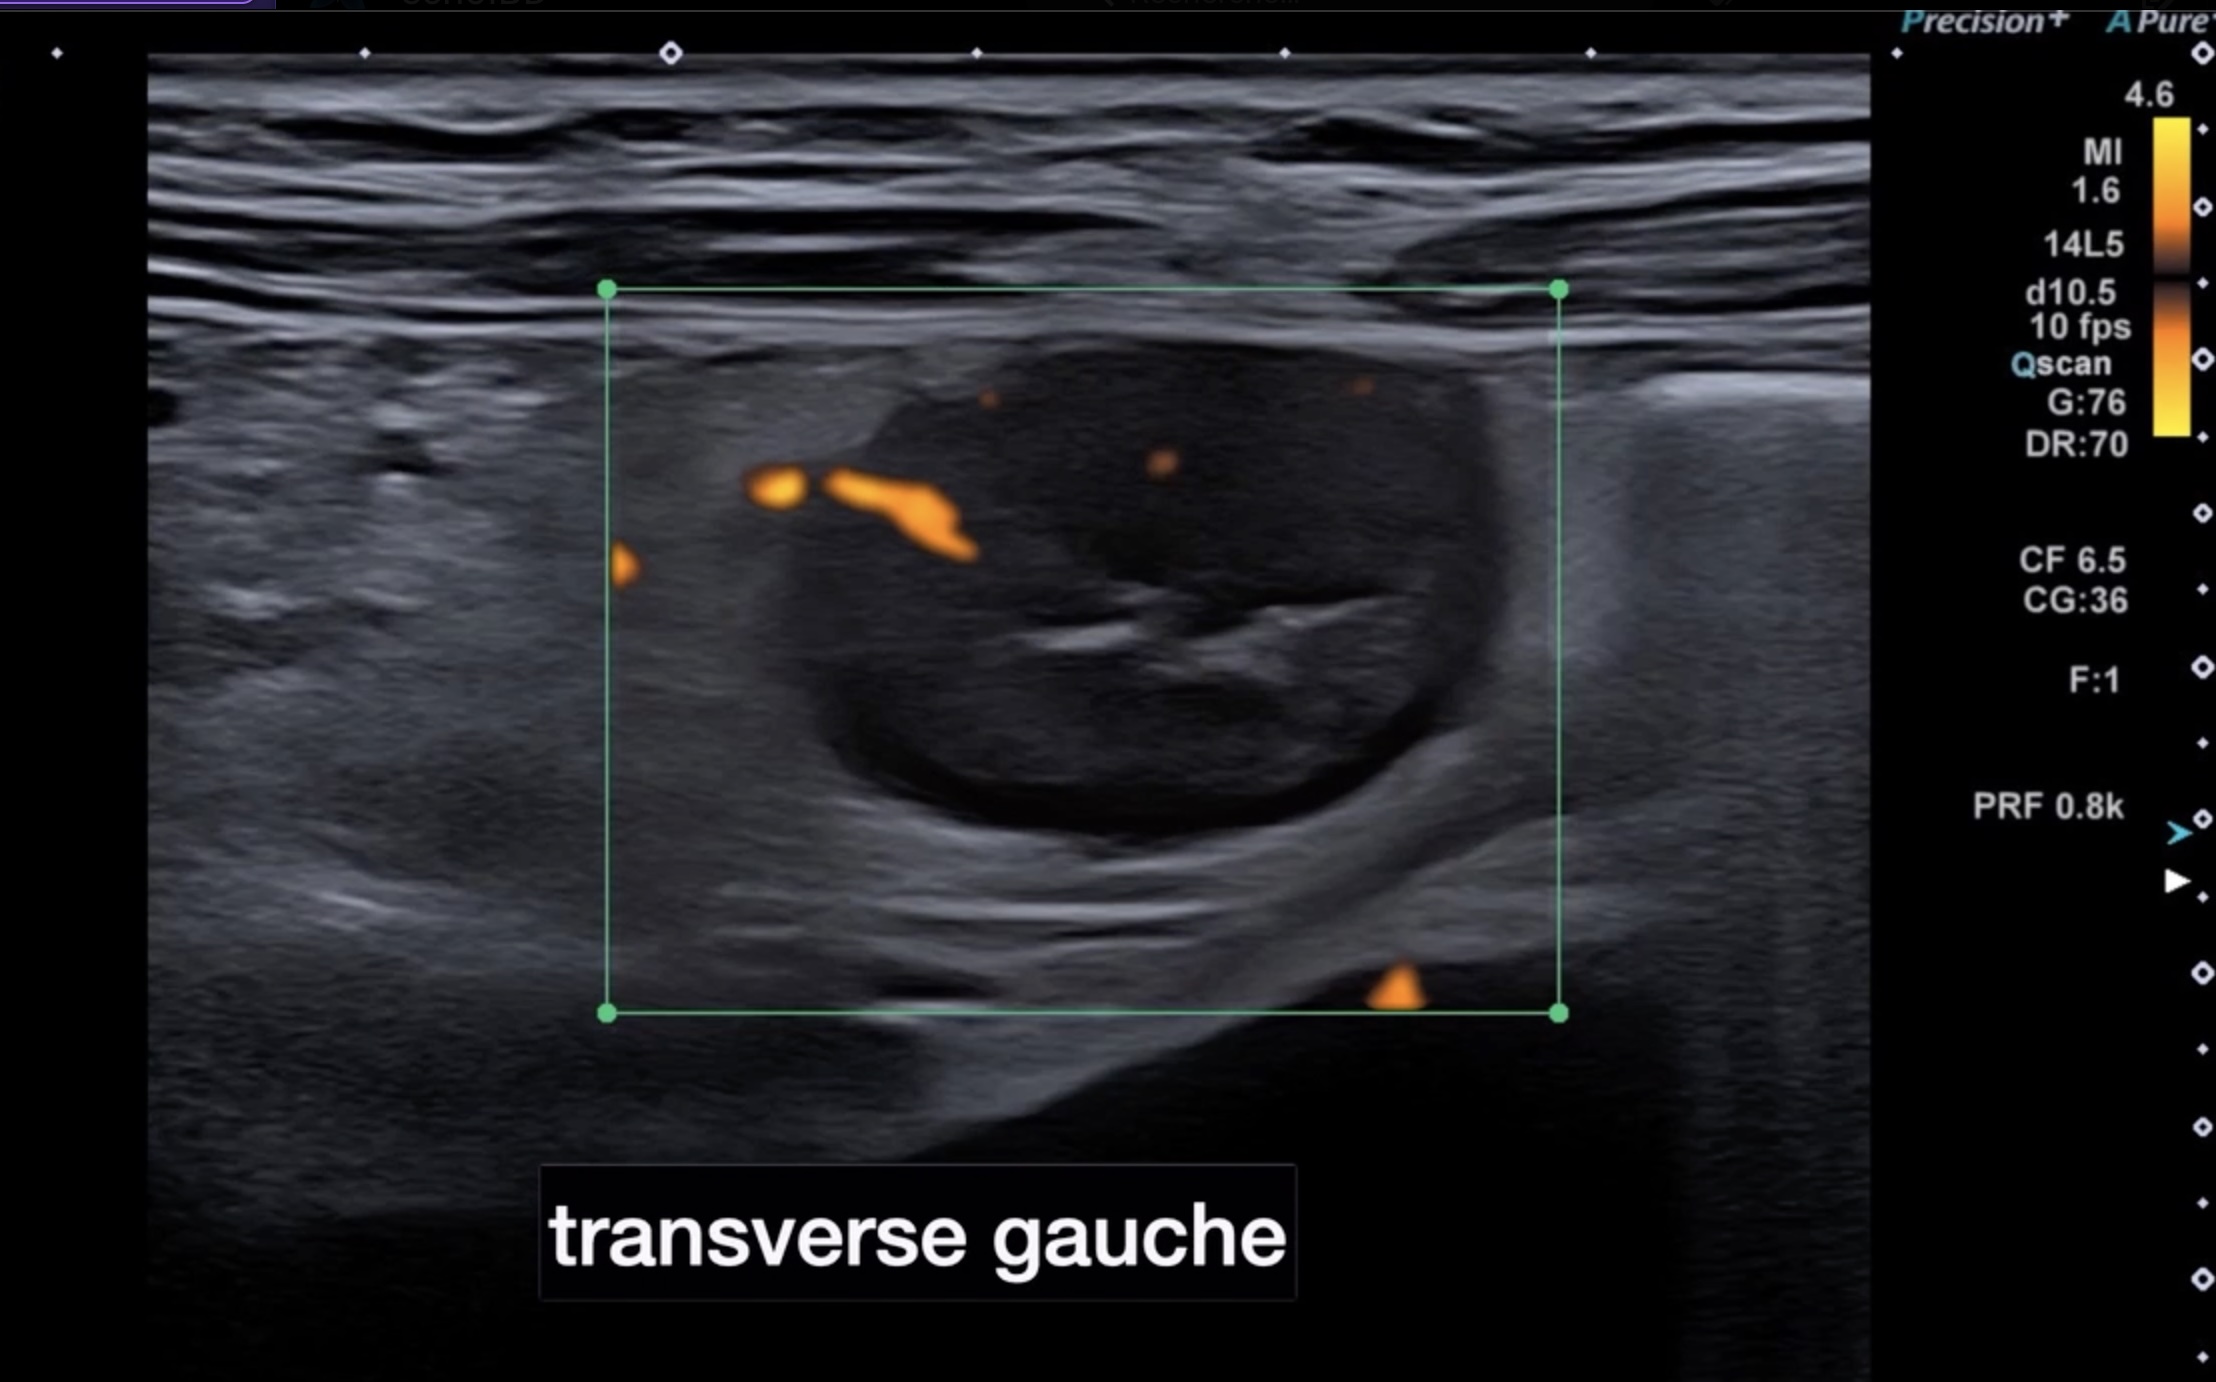

À gauche, lésions plus sévères avec disparition totale des couches, circonférentielle, très épaissie (7,5 mm), lumière diminuée en permanence, graisse très infiltrée et une activité doppler intense. En endoscopie la lumière est rétrécie, on voit une atteinte circonférentielle avec des ulcérations profondes on ne voit que l’orifice d’entrée des ulcères.

![]() Transverse droit et gauche |

![]() transverse gauche atteinte transmurale circonférentielle, sténose partielle de la lumière |

![]() Transverse gauche atteinte circonférentielle lumière rétrécie |